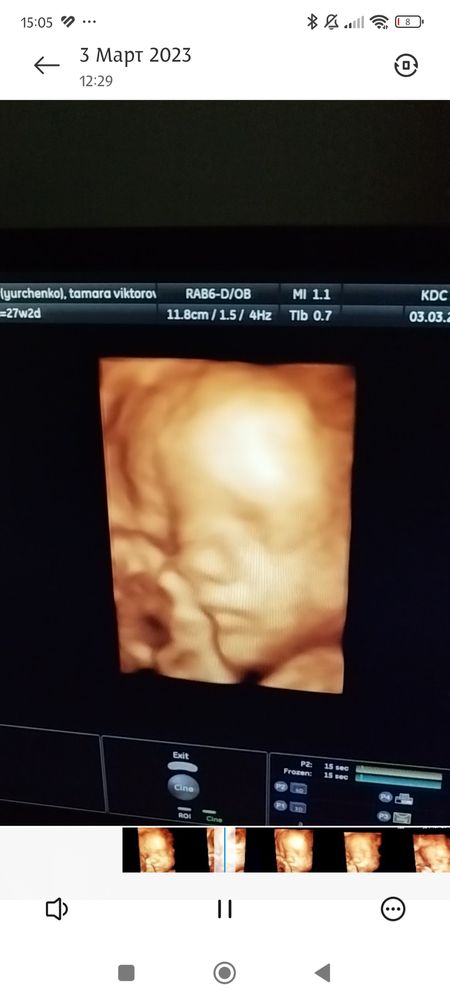

Девушка с книжкой

Вот недель в 25 - в принципе, довольно похожа, но надо приглядываться, потому что снимок узи не так чтобы очень чёткий))